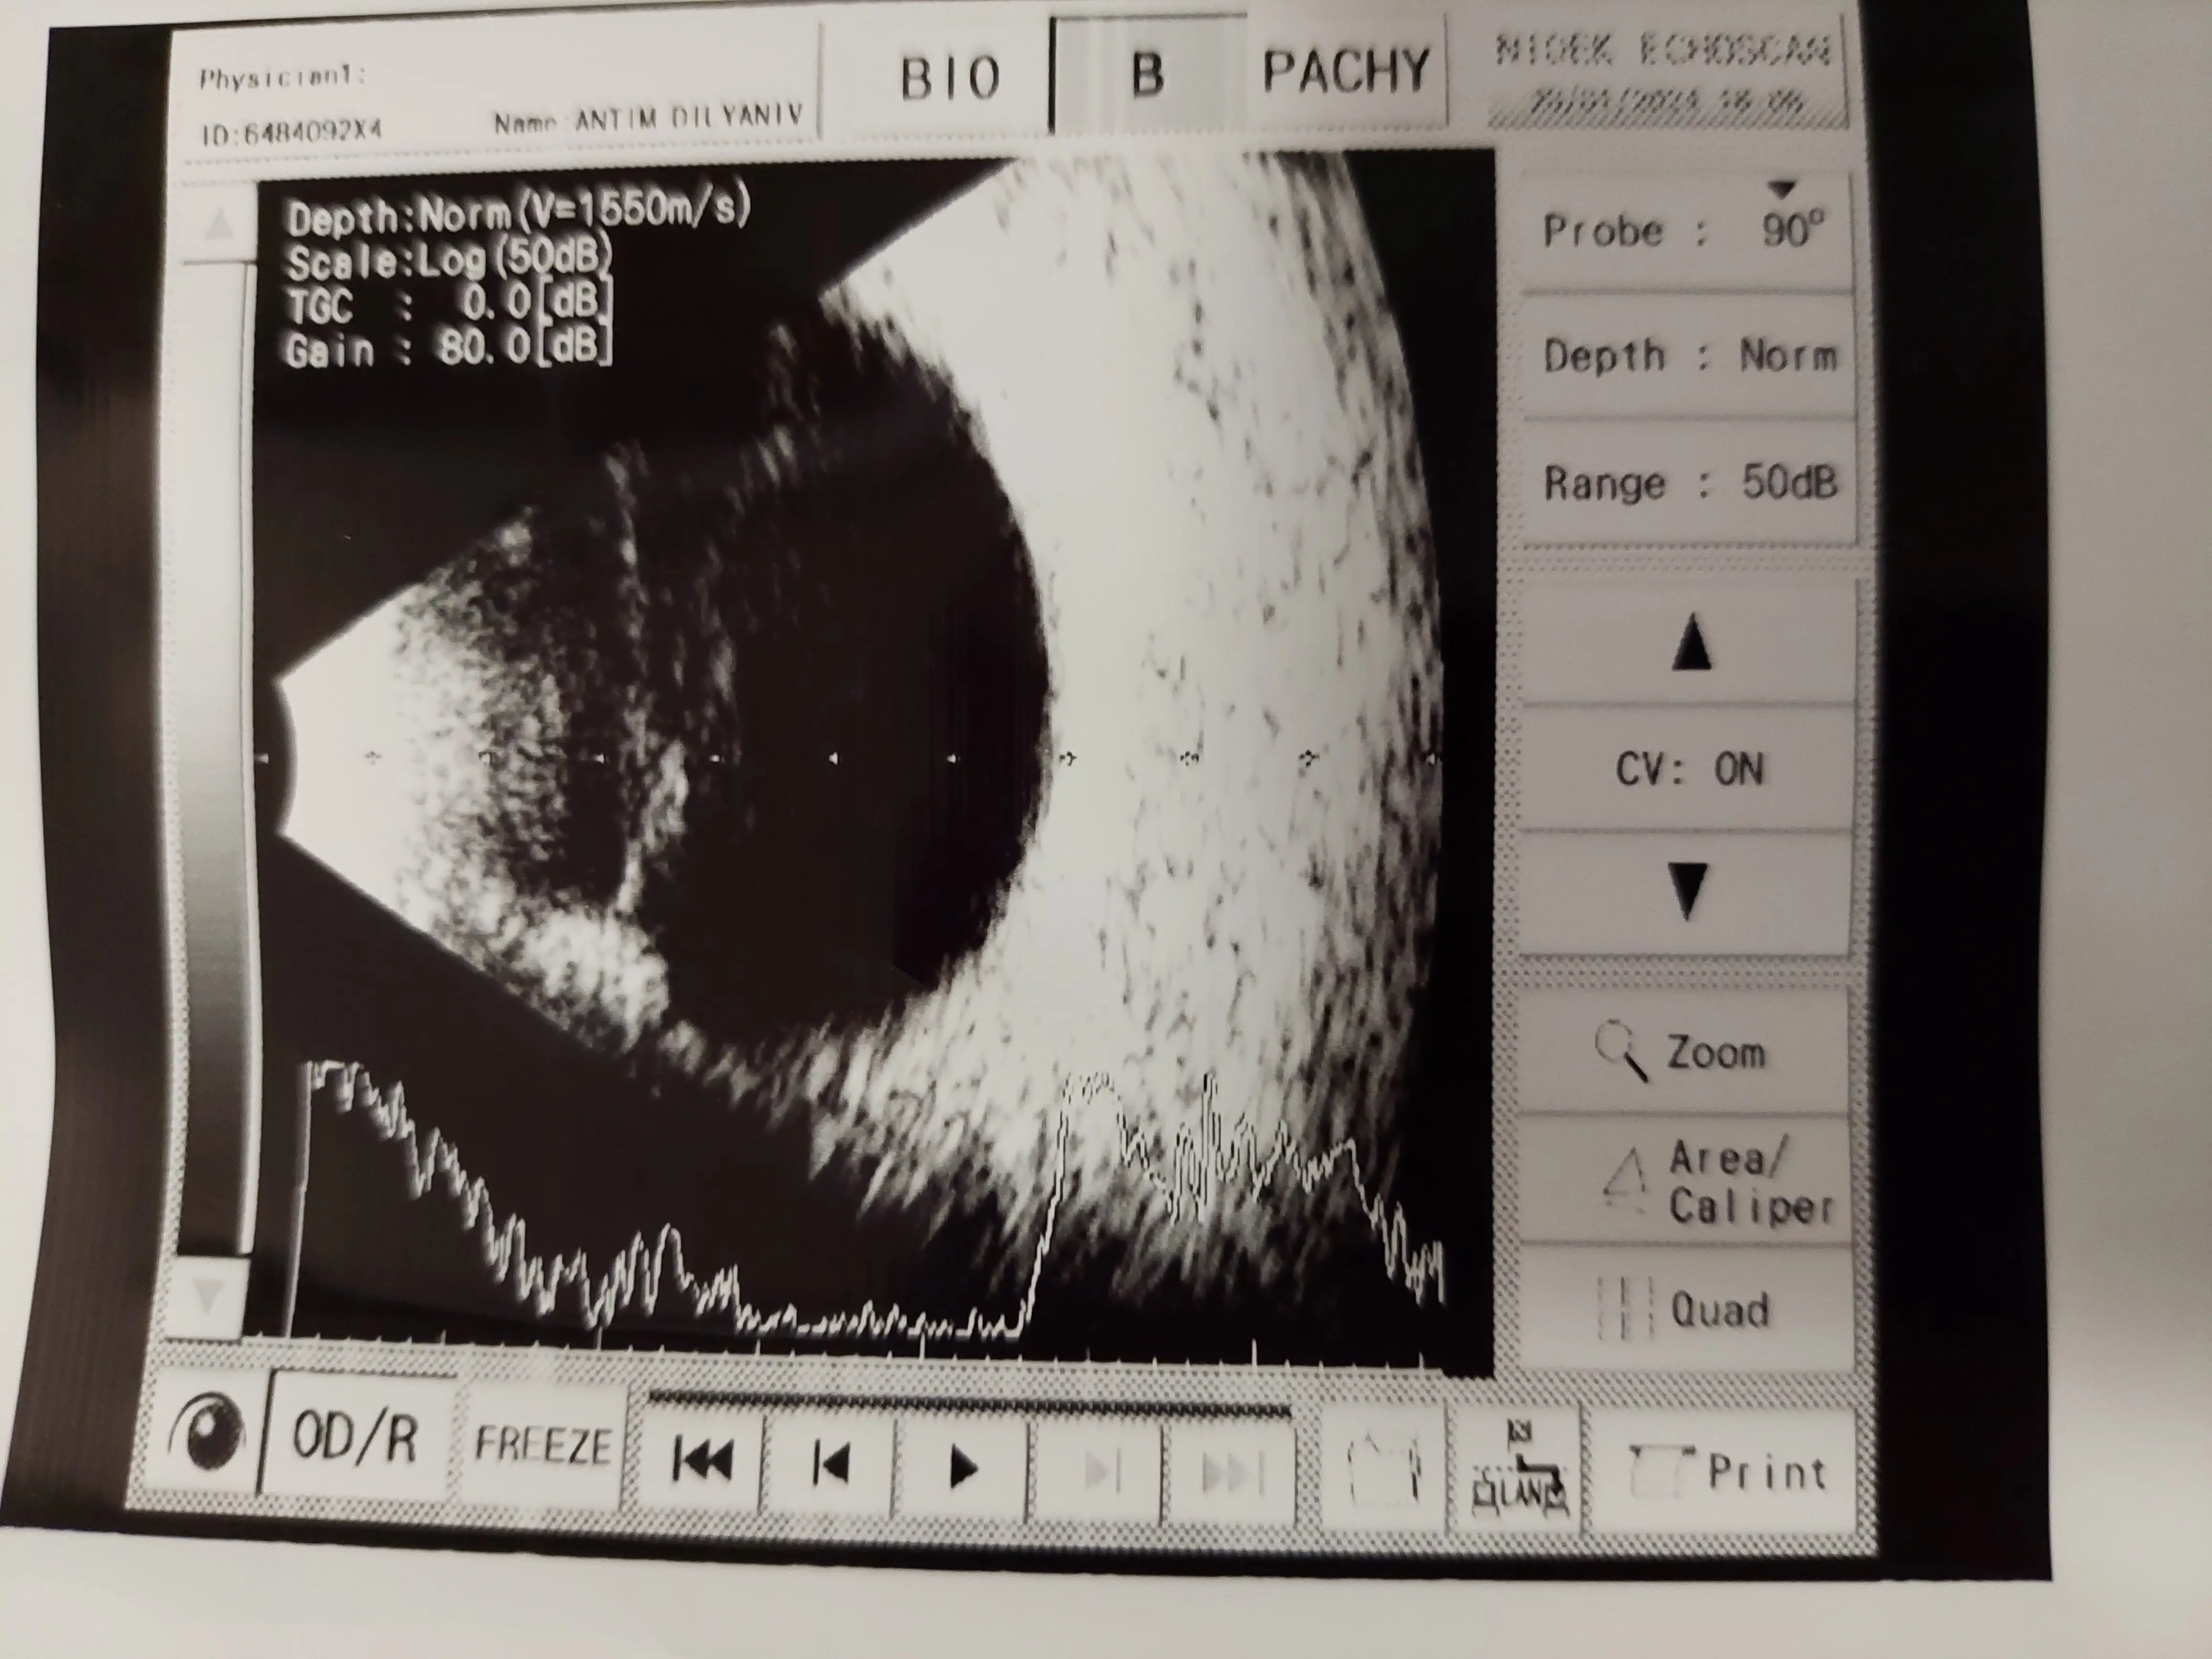

Мили хора, посетихме професор Алпер Агча, специалист по роговична трансплантация. Той потвърди диагнозата за силно изтъняване и помътняване, която изисква смяна, тъй-като цветната снимка е в лилаво, което показва необходимостта от трансплантация. Но се появи и друг проблем - кръвоизлив, като при това се превръща във фиброзна тъкан, захващаща се в ретината и има опасност от отлепване.

Професор Музалер, специалист по болести на ретината, препоръча спешна витректомия и трансплантация в една сесия до един месец най-късно.

Dear folks, we visited Professor Alper Agca, a corneal transplant specialist. He confirmed the diagnosis of severe thinning and clouding that requires replacement as the color photo is in purple, indicating the need for transplantation. But there was another problem - hemorrhage, with it becoming fibrous tissue, getting caught in the retina and in danger of detaching.

Professor Muzaler, a specialist in retinal diseases, recommended an emergency vitrectomy and transplant in one session within a month at the latest.